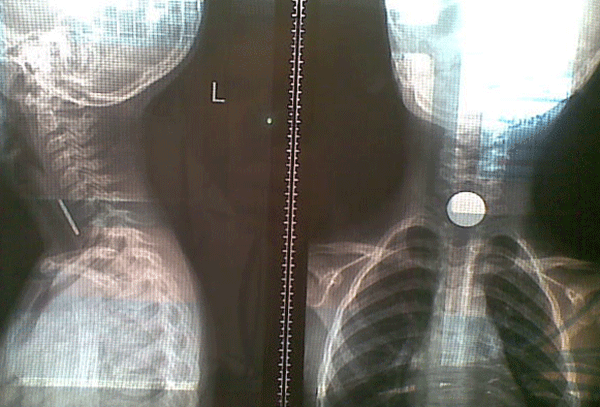

Saudi doctors saved a five-year-old local girl who swallowed a coin by mistake at her home in the Gulf kingdom, a newspaper reported on Saturday.

The child was rushed to hospital in the southern Najran town suffering from cough and breathing difficulties and images showed a coin was stuck in her pharynx.

‘Ajel’ Arabic language daily said doctors managed to extract the coin out of the girl’s throat after surgery and that she was allowed to leave hospital two days later.